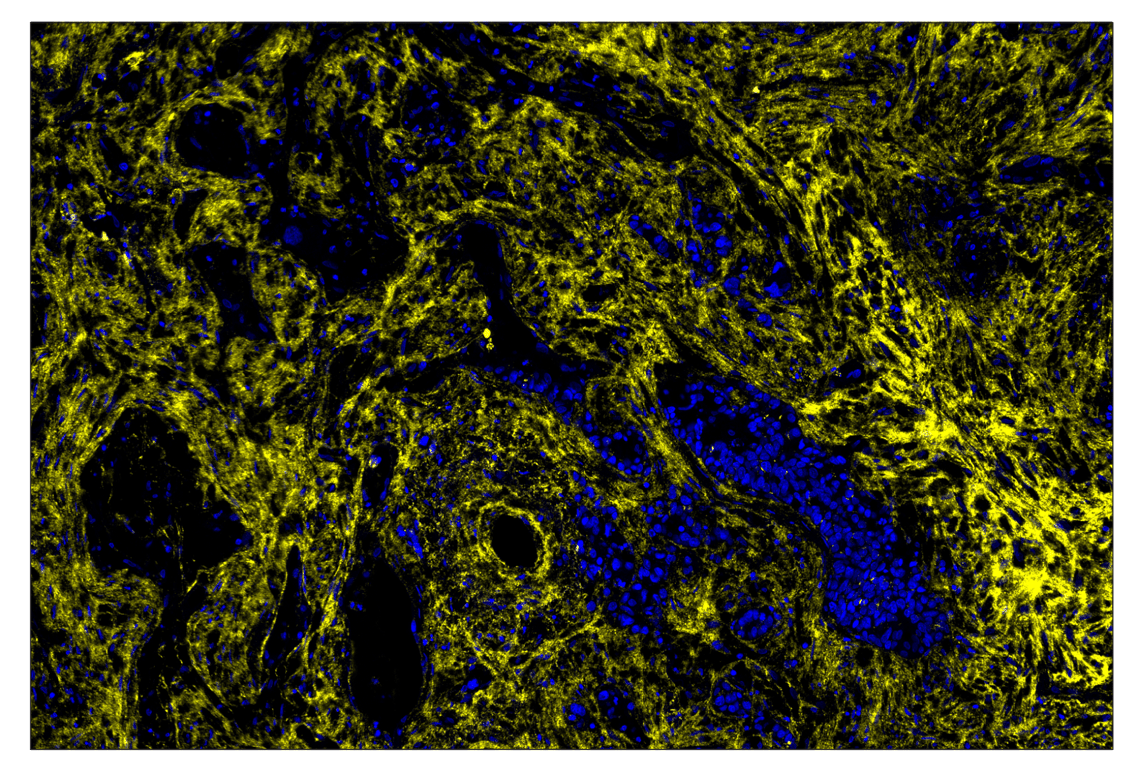

SignalStar® oligo-based multiplex immunohistochemical analysis of paraffin-embedded human large cell neuroendocrine tumor using Fibronectin/FN1 (E5H6X) Rabbit mAb (594; yellow) and DAPI #4083 (blue). Staining was performed on the BOND RX autostainer by Leica Biosystems.

Immunohistochemistry Image 2: Fibronectin/FN1 (E5H6X) & CO-0203-594 SignalStar<sup>®</sup> Oligo-Antibody Pair